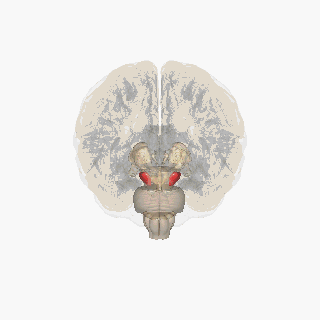

Substantia nigra highlighted in red. | |

The substantia nigra, along with four other nuclei, is part of the basal ganglia. It is the largest nucleus in the midbrain, lying dorsal to the cerebral peduncles. Humans have two substantiae nigrae, one on each side of the midline.